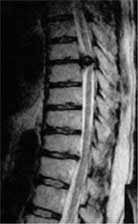

MRIを撮ると胸椎8-9間のヘルニアだと判明いたしました。

MRIを再び撮ると、今回はヘルニアではありませんでした。